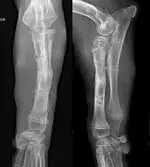

The puppy was sedated with xylazine, glycopyrrolate, and nalbuphine intravenously, and orthogonal radiographs of the left and right antebrachii were obtained. Radiographs of the right radius and ulna were normal. However, radiographs of the left antebrachium revealed caudolateral displacement of the radial head with normal positioning of the humeroulnar joint (Figure 1).

Figure 1: Orthogonal radiographs of the left antebrachium showing caudolateral displacement of the radial head